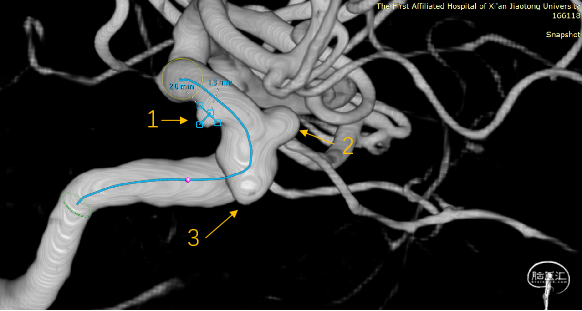

1:C6段,大小约2.9mm×2.0mm×1.3mm、瘤颈宽2.9mm;

2:C6段,大小约3.6mm×3.5mm×2.2mm、瘤颈宽2.9mm;

3:C5段:大小约3.5mm×3.3mm×2.4mm,瘤颈宽5.0mm;

经Fastrack微导管输送FD到位

缓慢回撤Fastrack微导管,FD头端在颈内动脉末端V形打开,确认FD远端锚定点位于A1分叉近端

继续缓慢回拉释放支架

虹吸弯处适当推拉,使支架贴壁良好

支架完全完全打开,完全覆盖全部动脉瘤

血流导向装置的应用可以显著改变动脉瘤腔内血流动力学,降低瘤壁剪切力,使血流转向,促进瘤腔内血栓形成;为血管内皮细胞生长提供了结构基础,降低瘤颈残留和动脉瘤复发。

本例病例,一箭三雕,密网支架可以简便高效地覆盖瘤颈,降低手术难度,提高有效性和安全性,长期效果良好。